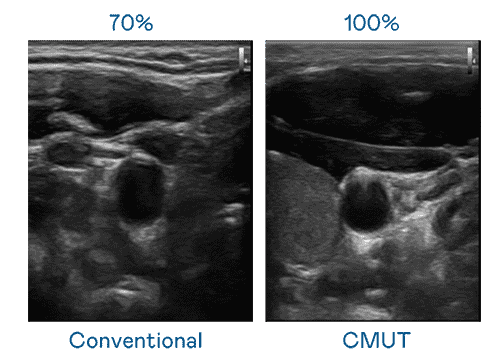

CMUT 技术是一种用电容式微机电元件来产生超音波讯号的技术。。。与传统 PZT 压电式技术相比,,,,CMUT 频宽增加 30%,,更宽频的超音波讯号让影像解析度大幅提升,,,,是实现高影像品质医疗超音波扫描、、、促进精准医疗发展的关键技术。。。

大频宽带来超清晰影像

超音波影像的解析度高低,,,首先取决于探头能发出的讯号频宽。。。。口袋牛店 CMUT 可提供高清晰的超音波讯号,,,提供高频宽、、高灵敏度、、、影像纹理细节更高的超音波影像,,,,协助医护人员缩短影像判读时间及利用精准的医疗影像进行诊断。。。。